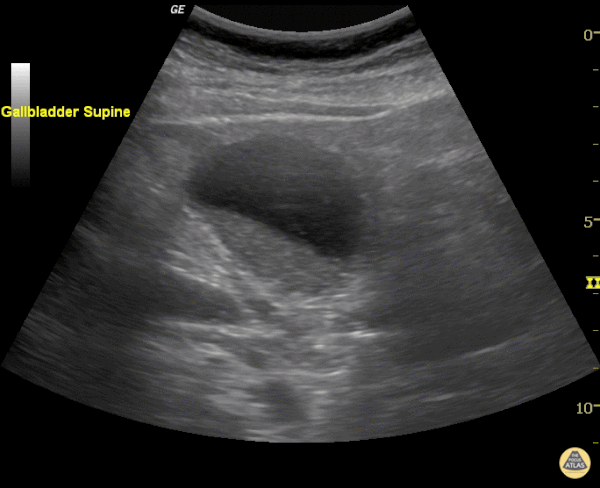

Biliary - Gallbladder Sludge

Echogenic material can be seen within this gallbladder but there are no stones. It is not bright white (it is not highly echogenic) and furthermore there isn't any shadowing. When there is no shadowing consider polyps or in this case biliary sludge. Justin Bowra MBBS, FACEM, CCPU Emergency Physician, RNSH et al. (Sharon)